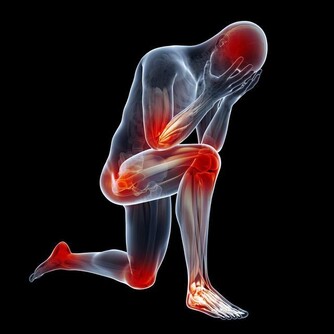

翻拍微信下同 其次當他入睡後依然維持了一個錯誤姿勢:側睡加頭低,導致頸部肌肉收緊,刺激了交感神經興奮,導致冠狀動脈平滑肌痙攣,心肌缺血,心梗而死。 頸椎病引起心臟病?是的! 專家說有可能!有一種心臟病就叫做頸源性心臟病,主要症狀包括如心前區作痛,心律失常,還會有胸悶不適感、心悸、氣促等。 看了下面數字,你怕不怕! 100個人中就有70個以上的頸椎病患者。 100個中風病症患者中有90%以上是由頸椎病引發的併發症。 100個腦癱病症患者中有63%以上是由頸椎病引發的併發症。 100個高位截癱病症者中有85%以上是由頸椎病引發的併發症。 100個猝倒死亡病症者中有95%以上是由頸椎病引發的併發症。 100個心肌梗塞病症者中有70%以上是由頸椎並引發的併發症。 100個腦血栓病症者中有80%以上是由頸椎並引發的併發症。 100個高血壓病症者中有60%以上是由頸椎並引發的併發症。 100個神經性胃潰瘍病症者中有75%以上是由頸椎並引發的併發症。 頸椎病有多要命?很危險! 更可怕的是,醫學上還發現頸椎病至少可引發全身70種病症,以下是幾種常見的病症。 1 吞咽不暢:吞咽時有梗阻感、食管內有異物感,少數人有噁心、嘔吐、聲音嘶啞、乾咳、胸悶等症狀。 2 視力障礙:視力下降、眼脹痛、怕光、流淚等,甚至還可能失明。 3 腹脹便秘:部分頸椎病患者因鄰近的頸交感神經受到刺激和損傷,使受其支配的內臟器官胃腸道蠕動減慢。 4 高血壓:血壓明顯升高,稱為「頸性高血壓」。由於頸椎病和高血壓皆為老年人的常見病,故二者常常並存。 5 胸痛:單側胸大肌和乳房疼痛,檢查時有胸大肌壓痛,這與頸六和頸七神經根受頸椎骨刺壓迫有關。 6 猝倒:站立或者走路時因突然扭頭出現身體失去支持力而猝倒,倒地後能很快清醒。 7 下肢癱瘓:早期表現為下肢麻木、疼痛、跛行,個別患者還有排便、排尿障礙,如尿頻、尿急或大小便失禁等。 8 老年痴呆:一旦頸椎間盤突出導致橫突孔變細、變形,會致使所供應的腦區發生供血不足,慢性腦缺血引起了遺忘等認知功能下降,長期以往最終會出現痴呆。 這頸椎病看著不起眼,可對我們的生命健康的威脅可是非常大! 奉勸頸椎不好的朋友千萬要當心,不要耽誤自己。在這裡提醒你,也希望你看到後提醒身邊的人:一定要關注自身的頸椎健康,別哪天被這頸椎病要了性命還不知道! 而很多人認為頸椎病不是很要緊的病,休息休息就好了,但是拖延下去,治療會越來越難,有的甚至要做手術治療,更嚴重的估計就會重演李建華的悲劇。所以勸大家及早預防,儘早治療! 脖子為什麼一轉就響? 因為我們身體的氣血供應不上,導致我們身體在變硬,關節在處於缺血狀態下的干磨。 氣血雙虧的身體相當於車軸里沒了油,很多人騎過自行車,知道如果車軸里缺油了,會感覺怎樣?一定是騎著費勁,一定會感覺裡面的滾珠轉動不靈活且有響動,有點類似我們的脖子響。只不過,自行車軸轉動靠的是油,而我們骨頭之間的轉動靠的是血液罷了。當我們血氣雙虧的時候,我們的骨關節之間的椎間盤,沒有充足的氣血供應,會形成干磨的情況,響動也就自然產生了。 骨關節為什麼會有病變? 1生理結構 人的頸椎和腰椎特別容易出問題,但胸椎卻好得多。這是因為我們的胸椎周圍有肋骨牽拉保護著,形成了一種力的相互作用,以確保我們的胸椎能夠保持中正。但是,頸椎和腰椎就不同了,它們沒有肋骨牽拉固定著,它們靠的是多組韌帶和小肌肉群。如果這些組織發生問題,就會導致我們的頸腰椎出問題。 2工作姿勢 當肌肉長期處於緊張狀態,就會感覺肌肉酸痛。正常情況下,如果胳膊腿酸了,我們活動一下,這樣的現象會很快消失,但是,用電腦就不一樣了,由於我們是長時間處於微弱的緊張狀態,這就好比溫水煮青蛙一樣,等我們查覺的時候,就已經晚了。它造成的後果就是,頸腰椎周圍的韌帶由於得不到充足的氣血供應,就會慢慢形成鈣化,兩側的牽拉受力開始不均勻,久而久之,椎間盤就會突出,擠壓周圍的組織和神經,頸腰椎病就會形成。 3工作環境 如果再加上工作環境的寒和濕比較嚴重,比如,在地下室工作、在空調底過的情況下工作,都會造成環境中的寒和濕進入到體內,特別是對於那些氣血本來就不夠通暢的肌肉和韌帶,會形成潛在的影響,加重了病變部位的病情。 4過食碳酸飲料 碳酸飲料會導致內脫鈣,久而久之,我們的骨頭變會得非常的疏鬆,那個時候,就不單純是骨頭響的問題了,而且還很容易導致骨折。 我們該如何調理? 下面介紹簡單易學的保護頸椎,甚至可以治好頸椎病的方法,大家一定要記好了! 1多多活動 天天以電腦為伴的朋友,用一會兒電腦,就要起來活動一下,同時活動一下脖子,但千萬不要做360度的圓周運動,只作90度向左轉,向90度的向右轉的動作,以確保我們脖子兩側的韌帶在短時間內,都能夠得到均衡的牽拉,以改善局部供血。而且切記動作要緩慢。 2不要讓頸部受涼 其是不要讓頸椎吹到冷風。頸椎受涼之後寒濕之氣很容易進入體內,而加重頸部韌帶的鈣化。 3杜絕碳酸飲料 減少包括可樂在內的一切碳酸飲料的攝入,因為這種溫水煮青蛙的過程是漸進的,因此很難被人們重視。 4打通經絡 這點最為重要。如果是脖子不舒服,最簡單的方法就是以自己的下巴寫米字,一天做一次即可,或在桌子邊擱後溪穴,以確保頸椎部的血液循環,使自己的頸椎摸著是溫暖的,而不是冰涼的。 5滾一滾、滾出好脊椎 站立歪斜或坐姿不端正、習慣性翹腳、長時間玩手機或者是坐在電腦前都會造成我們脊椎歪曲不直,脊椎一旦彎曲歪斜,很多毛病會跟著來。 中老年朋友可以常常做滾背的動作,矯正脊椎,甚至有人長了骨刺也可以治癒哦!每天勤快108下(來回一次算一下),骨刺免開刀,不用快慢慢做,矯正脊椎自己來! 滾背方式: 1、並腿屈膝坐在地上,兩手環抱住小腿,自然呼吸別太急促,收腹拱背,身體往後從尾椎、腰椎一節一節觸及地面,剛開始腳還先不用越過頭,多做幾下後再視自己身體狀況,然後滾到胸椎、頸椎,腳尖朝上,漸漸地雙腳越過頭,腳打直腳尖著地。